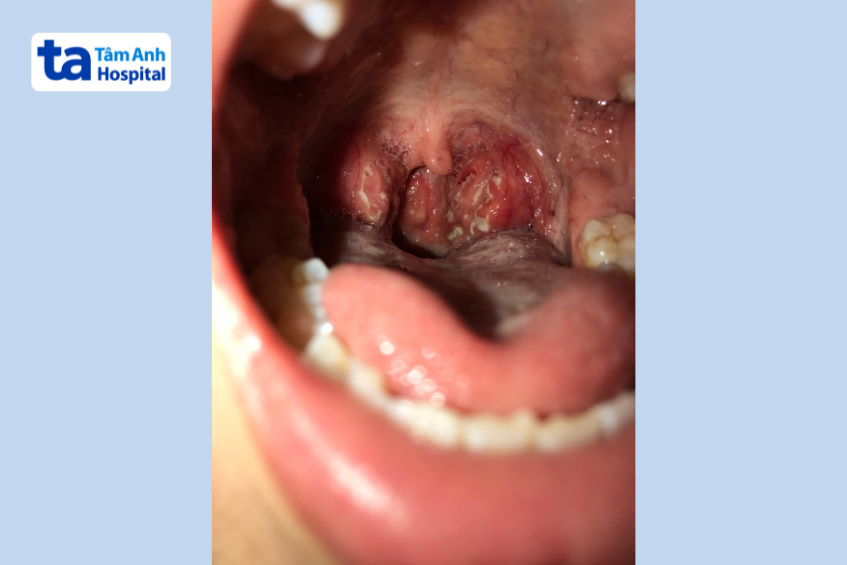

Bạch hầu (Diphtheria) là bệnh nhiễm khuẩn cấp tính xuất hiện giả mạc ở các tuyến hạnh nhân, hầu họng, thanh quản, mũi, do chủng vi khuẩn có tên là Corynebacterium diphtheriae gây ra. Bệnh thường xuất hiện ở da, các niêm mạc khác như kết mạc mắt, tai và bộ phận sinh dục.

Đây còn được gọi là bệnh bạch hầu họng. Đây là loại phổ biến nhất (chiếm 40-70% trường hợp), ảnh hưởng đến mũi, họng, amidan và thanh quản (hộp thanh quản) của người bệnh. Các triệu chứng ở người nhiễm bệnh bệnh ở đường hô hấp thường khác nhau tùy thuộc vào vị trí mà vi khuẩn khu trú. (3)